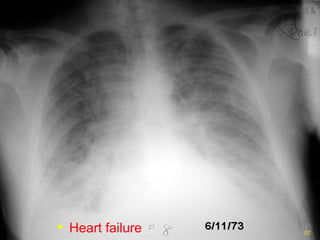

Congestive Heart Failure Increased heart size:  cardiothoracic ratio  >0.5 Large hila with indistinct markings Fluid in interlobar fissures Pleural effusions, alveolar edema

Heart failure